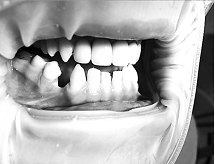

В ході власної практичної апробації даного методу

реставрації реконструкція форми поєднувалась з корекцією кольорових

характеристик зубів та ясен, а об’єм втручання визначався в залежності від

розмірів дефекту або дефіциту твердих і м’яких тканин (рис. 1-2).

Рис. 1. 45 зуб: вигляд до та після відновлення

дефекту рожевим композитом

В результаті проведених реставрацій вдалось

відновити форму та розмір проблемних зубів, параметри їх світлопроникності,

особливо опалесценції, транслюценції та прозорості на межі рожевої та білої

естетики, а також особливості структура поверхні в області ясен. Аналогічно

успішні результати відновлення пришийкових дефектів в області рецесії ясен були

описані в роботах Wahbi M. A., Tayeb H. (2013) [11] та Dhingar D., Gupta A. K.

(2016) [12].